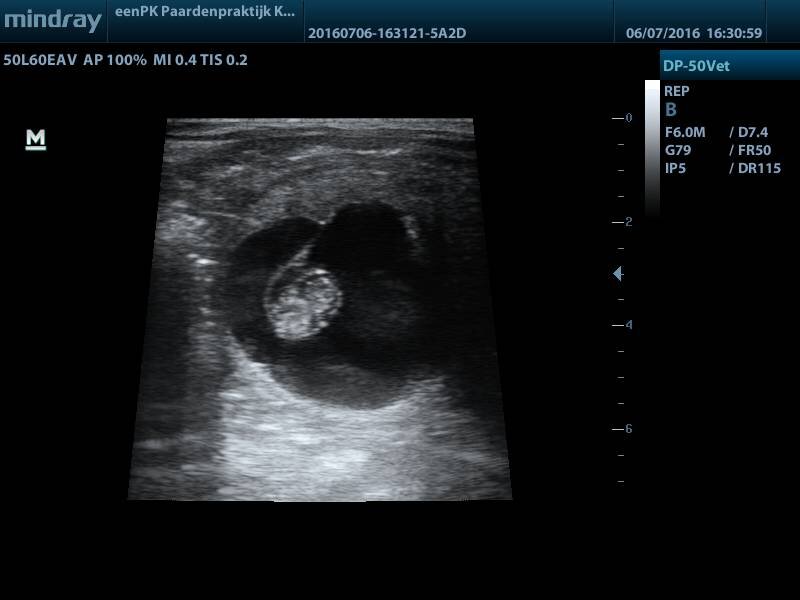

Eerst twee weken was ik er niet zo mee bezig, maar dan komt de periode dat ze toch hengstig zouden moeten gaan worden als het niet gelukt zou zijn. Je hoopt zo dat je niks ziet dat je niet wilt zien. Je dekt jezelf toch in: Er staat geen hengst in de buurt, dus misschien zijn ze wel hengstig geworden maar zie ik het daarom niet..06/07/2016, tijd voor een bezoekje van de dierenarts! Ik was stiekem toch wel een beetje zenuwachtig. We beginnen met Violetta:

Al snel is het te zien, heel netjes drachtig!

Uitgerekend: 4-9 mei 2017